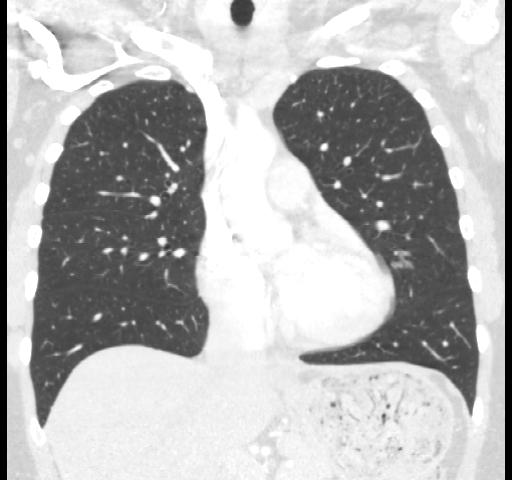

40 year old female. Breast implants 17 years ago, most likely Dow Corning. Symptoms from upper body for 6-7 years. Pain in breasts, ribs, back, neck. Skin rash. Headache and dizziness, weakness, numbness and vision disturbing. Sudden sleep episodes. Painful lymph-notes. These images are from 2010 and diagnose results were "No findings". Patient is scheduled for explantation in mid Feb. 2012